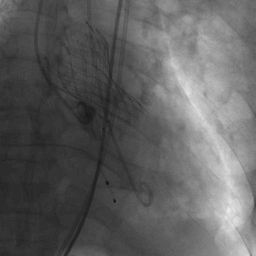

跨瓣成功后,将Lunderquist导丝送入左心室,23 mm球囊预扩张,VenusA-Valve L29型号瓣膜精准定位并释放,术中造影及超声反馈良好,瓣膜形态良好,结果满意。

球囊预扩图

瓣膜释放定位